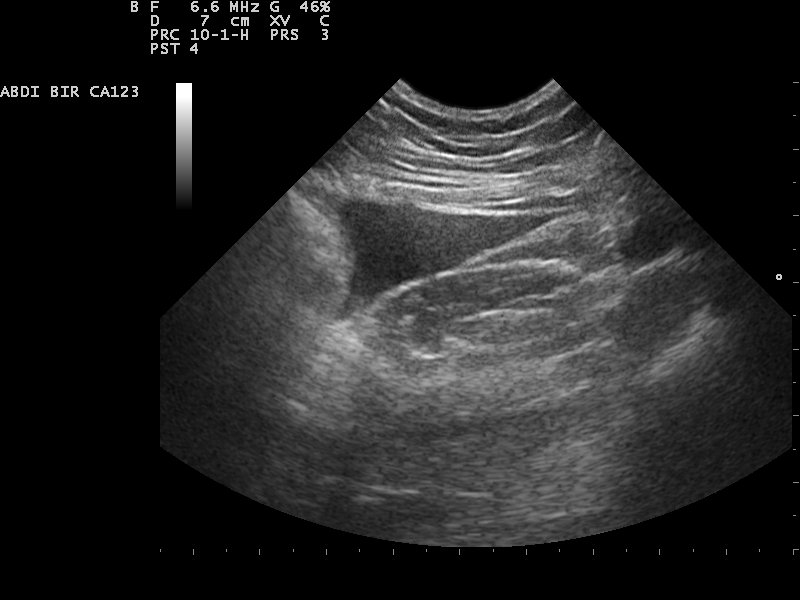

Ultra zvučnim pregledom abdomena mogu se videti : jetra, žučna kesa i žučni putevi, pankreas, slezina, bubrezi, nadbubrežne žlezde, mokraćna bešika, prostata, aorta i paraaortne limfne žlezde. Ultra zvukom se ne mogu videti želudac i creva.

UZ pregled žučne kese je jedan od najčešćih razloga za izvođenje ultra-zvučnog pregleda abdomena koji se izvodi ako postoji sumnja na postojanje žučnog kamena ili radi praćenja veličine ranije dijagnostikovanog žučnog kamena. Osim kalkulusa ( kamena ) žučne kese moguće je pratiti i polipe ali i žučni mulj

UZ pankreasa prati se veličina anatomskih delova pankreasa ( glava, telo i rep ), struktura, oblik

UZ slezine prati se njena veličina, oblik, struktura, odnos sa okolnim strukturama